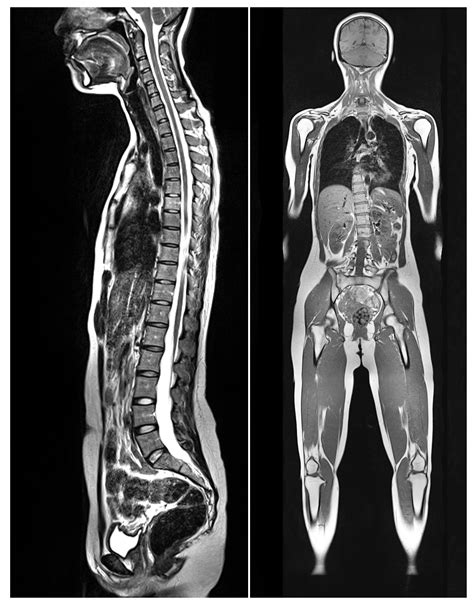

In the realm of medical diagnostics, the MRI Full Body scan has emerged as a powerful tool, offering unparalleled insights into the human body's internal structures. This non-invasive imaging technique uses magnetic fields and radio waves to produce detailed images of organs, tissues, and other internal structures. Unlike traditional X-rays or CT scans, MRI Full Body scans do not expose patients to ionizing radiation, making them a safer option for repeated examinations.

An MRI Full Body scan is a comprehensive diagnostic procedure that captures images of the entire body. This type of scan is particularly useful for detecting a wide range of conditions, including tumors, infections, and abnormalities in the brain, spine, joints, and other organs. The scan provides high-resolution images that allow healthcare professionals to make accurate diagnoses and develop effective treatment plans.

One of the key advantages of MRI Full Body scans is their ability to differentiate between various types of soft tissues, making them particularly useful for diagnosing conditions that affect the brain, spinal cord, muscles, and joints.